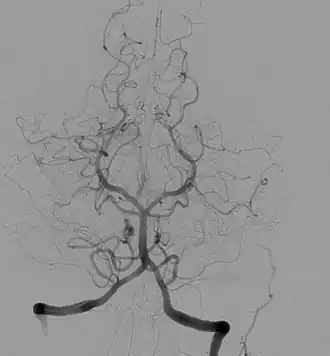

Angiogram van de cirkel van Willis

Angiografie is een afbeeldingstechniek in de geneeskunde, waarbij bloedvaten en hartkamers met behulp van contraststof worden afgebeeld met röntgenfoto's. De afbeelding die ontstaat heet angiogram. De naam komt van de Oudgriekse woorden ἀγγεῖον, angeion, vat en γράφω, grápho, schrijven. Angiografie betekent letterlijk afbeelding van bloedvaten.

De Portugese neuroloog Egas Moniz heeft de techniek in 1927 ontwikkeld. Hij was ook operacomponist. De eerste toepassingen waren vooral gericht op indirecte lokalisatie van bloeduitstortingen en hersentumoren onder het hersenvlies. Deze toepassing was met de komst van de computertomografie in 1971 en de magnetic resonance imaging in 1980 niet meer nodig, omdat met deze apparatuur tumoren kunnen worden bekeken, maar voor andere toepassingen wordt angiografie nog wel gebruikt, bijvoorbeeld bij dotteren. De cirkel van Willis kan met angiografie zichtbaar worden gemaakt.